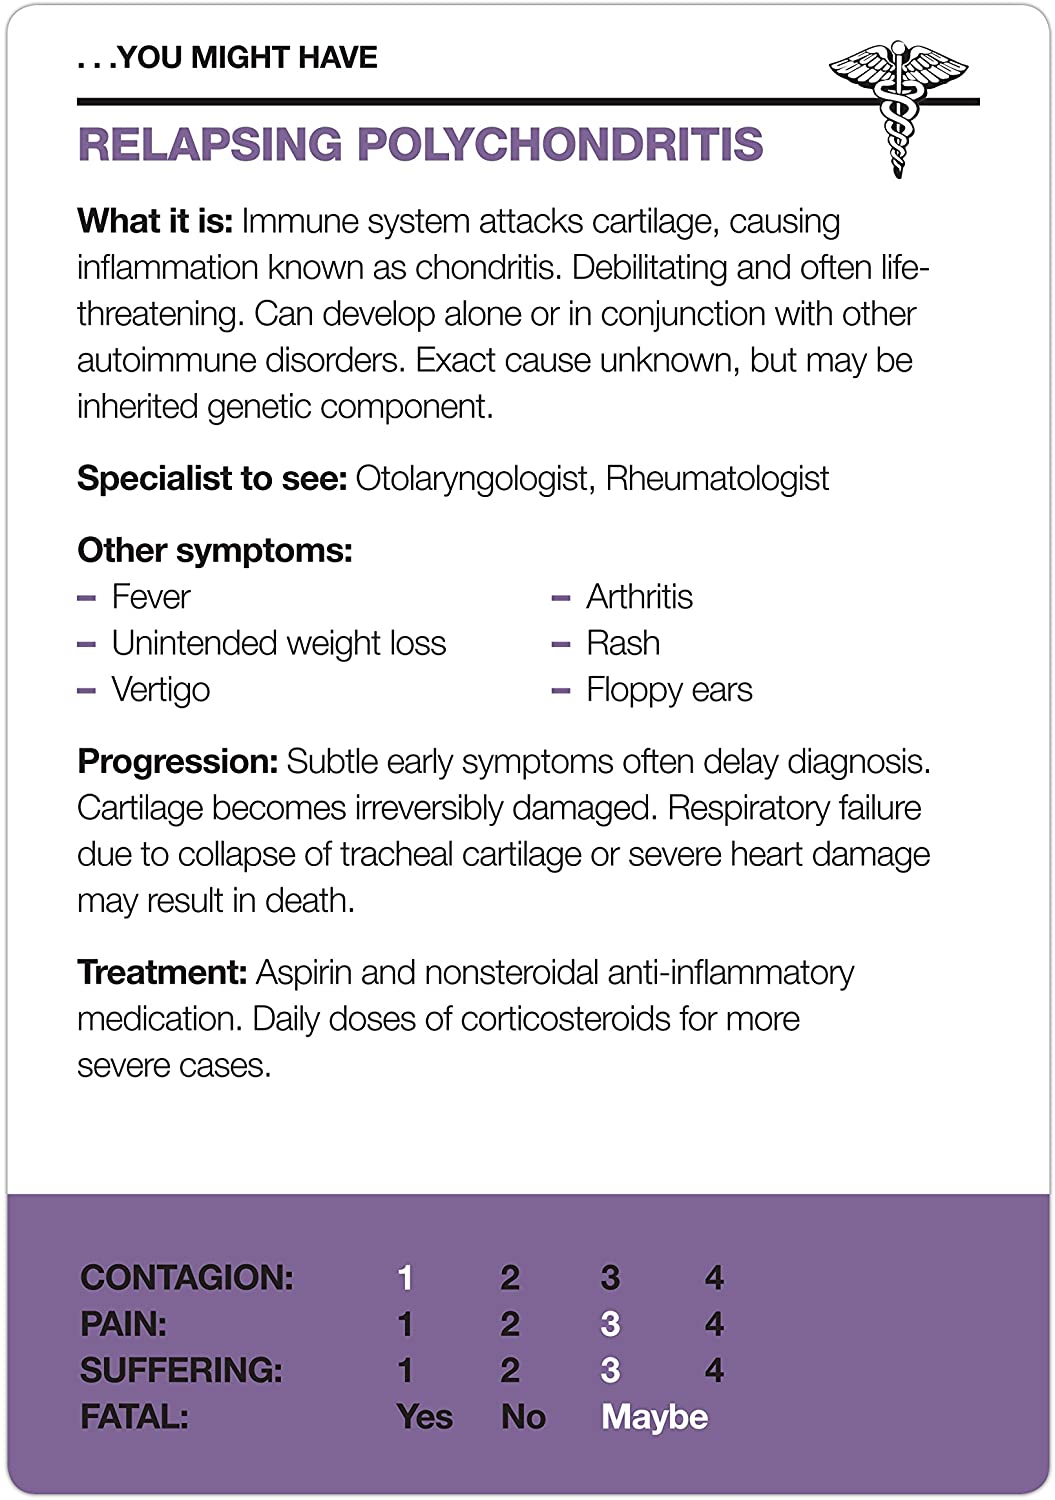

- With this deck of Fifty Things That Might Kill You, pick your symptom and pick a card (or cards) to see what rare, multisyllabic, and possibly fatal disease you might have

- A symptom checker that mixes dark humor (and actual facts) for hypochondriac fun!

- Warning: self-diagnosis may cause fear of serious illness, phantom symptoms, unhealthy coping mechanisms, self-absorption, anxiety, oversharing, sweaty palms, and hyperventilation